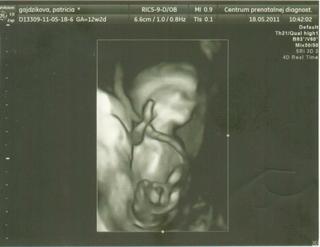

@topa blahoželám krásna fotečka

ahojte tehulky, tak som doma od lekára, všetko je ok babo ma asi 14 - 15 cm, srdiečko som aj počula aj videla aj bábo aj môj muž bol a videl a máme aj fotečky + video na usb kľúči. ešte sa nedalo povedať pohlavie,ale lekár vravel že no môže to byť dievčatko čo ma mooooooooooc tešíííííííííííííííííí 🙂 o týždeň mám volať na výsledky z genet. testov.